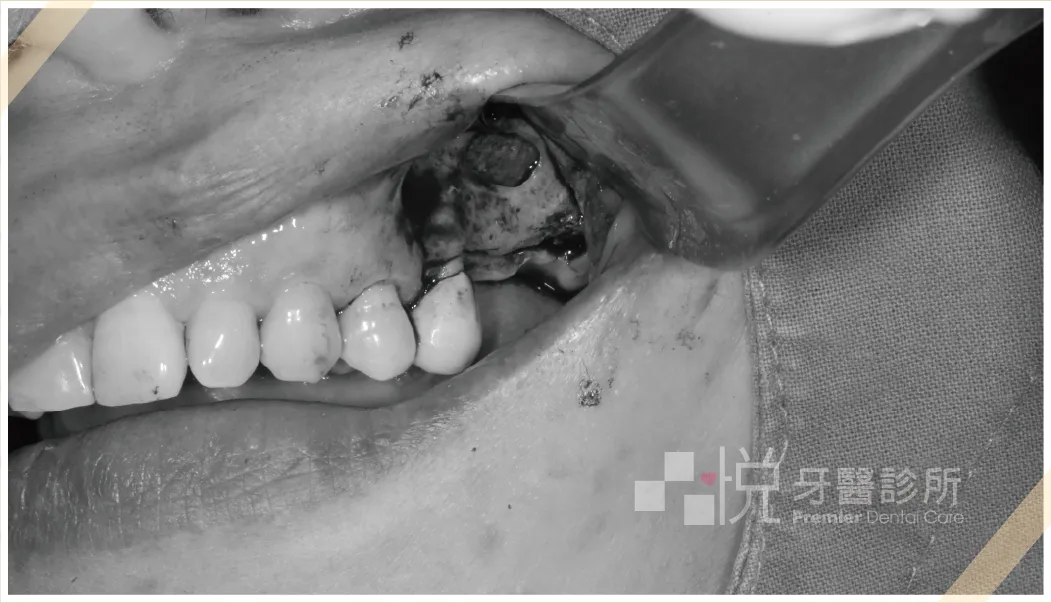

➋ 於要鼻竇增高之處形成骨窗,先把鼻竇膜露出。

➌ 使用器械把鼻竇膜往上剝離,並向騰出來的空間填塞骨粉